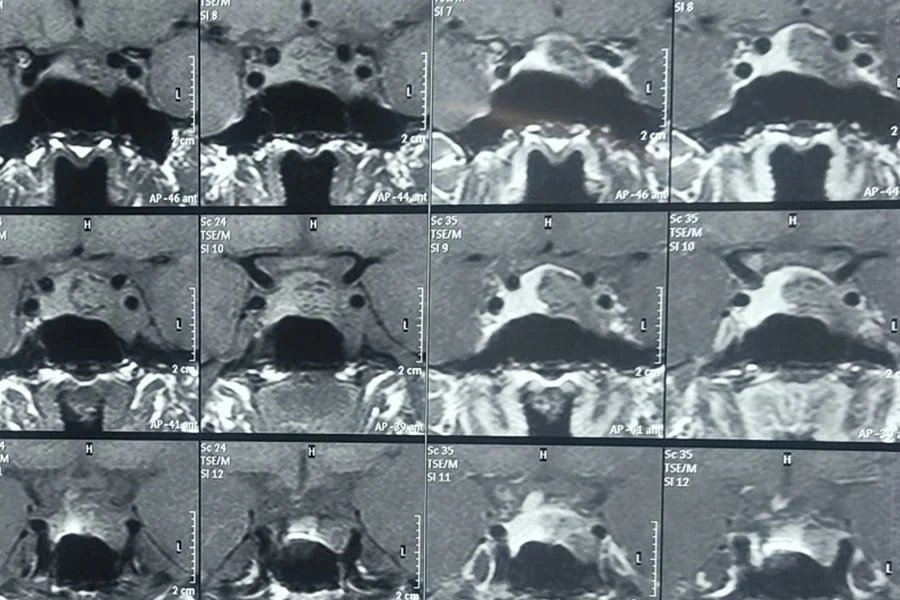

Pituitary surgery is performed to treat tumors or disorders of the pituitary gland, such as pitutary macroadenomas causing hormonal imbalance or pressure on surrounding structures like the optic nerves, cavernous sinus and carotids. Common symptoms include visual disturbances, headaches, and endocrine abnormalities.

Mostly they are carried out using endoscopic transnasal approach, accessing the gland through the nasal passages. All complex skull base procedures, including craniotomy when required, are performed in close collaboration with an experienced neurosurgeon as part of a multidisciplinary team to ensure optimal patient safety and outcomes.

The goal is safe tumor removal while preserving normal pituitary function and vision. Postoperative care includes hormonal evaluation and regular follow-up imaging to monitor recovery and detect recurrence.